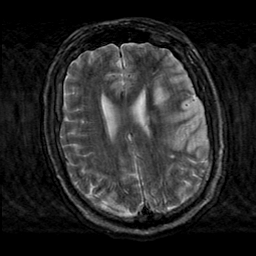

Subacute Stroke, overlay -- Slice #17

[Home][Help][Clinical] Slice 17